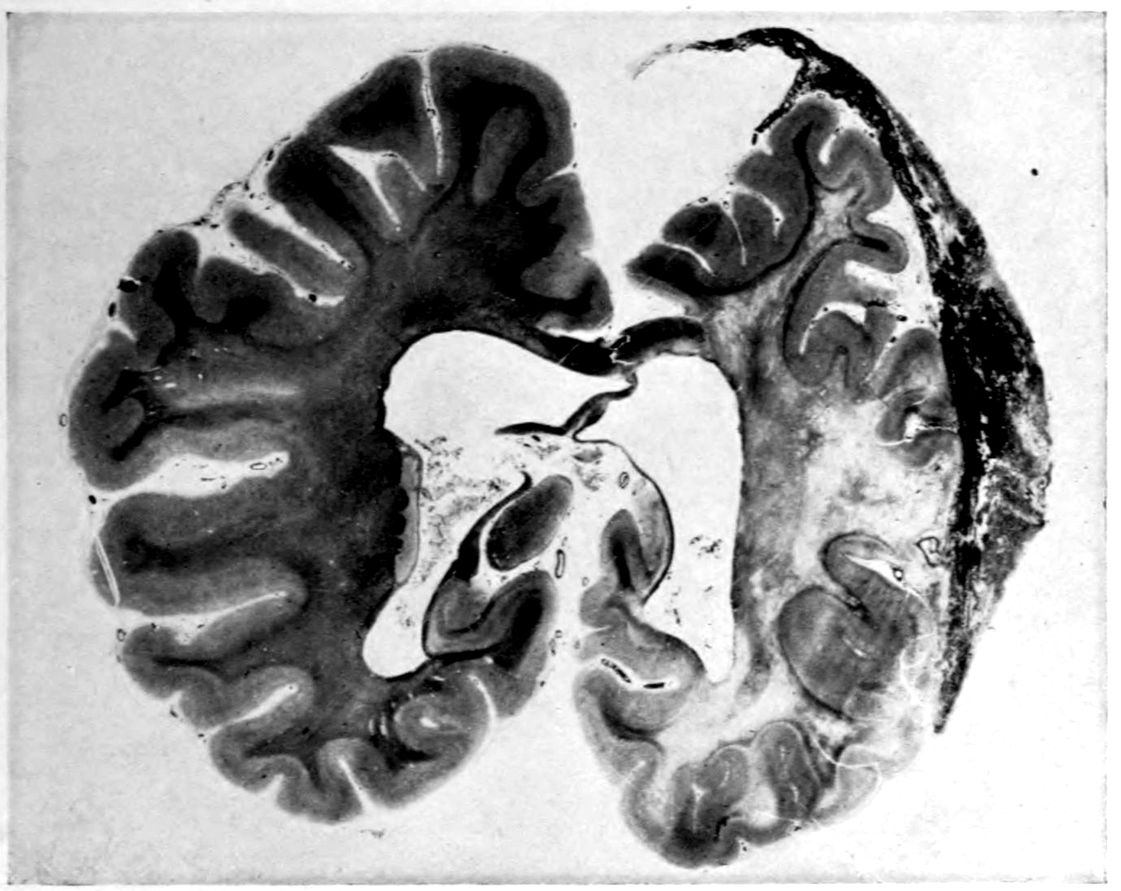

Vascular neurosyphilis—effects of syphilitic thrombosis of Sylvian artery 10 years before death. (Case 4.)

Case 4. (See previous figure for brain lesion.) Three levels of the spinal cord showing unilateral pyramidal tract sclerosis, 10 years after cerebral thrombosis.